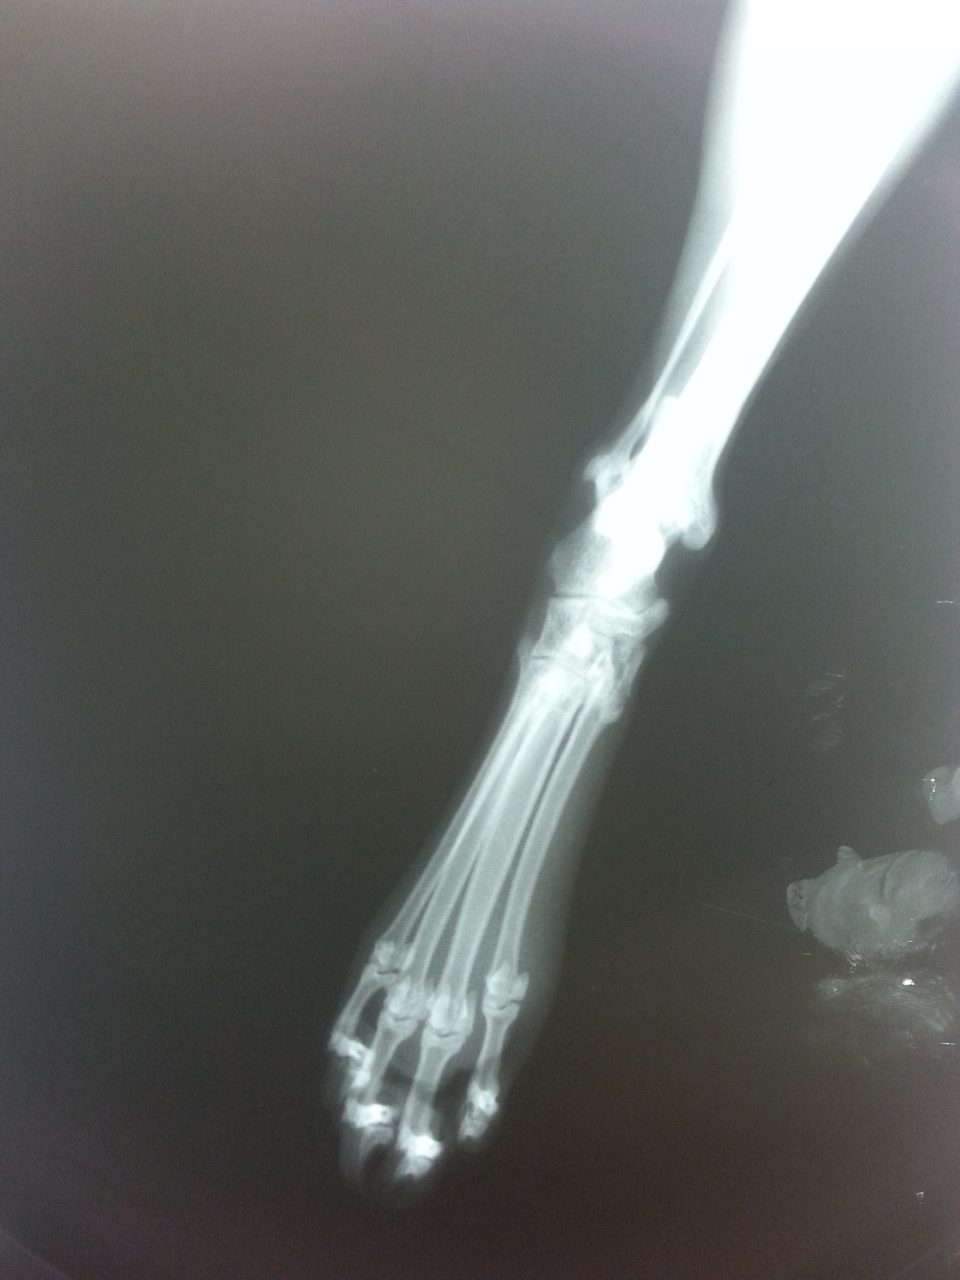

Situada en la pata delantera por debajo del codo, la muñeca es especialmente propensa a las lesiones. Mientras que los esguinces son más comunes en las caderas y los muslos debido al sobreestiramiento, los esguinces afectan a los ligamentos (tejidos) que conectan los huesos, especialmente los de la muñeca y la rodilla. Los esguinces de muñeca del perro pueden ser causados por un aterrizaje brusco desde el coche o por un ejercicio brusco.

Los esguinces presentan muchos de los mismos síntomas que las distensiones y daños musculares, las fracturas leves, la degeneración ósea e incluso las afecciones cancerosas. Esto hace que la confirmación de la condición por un profesional veterinario sea muy valiosa para determinar el plan de tratamiento correcto.

Un esguince de tobillo es una lesión de los tendones, ligamentos y/o los músculos relacionados con esa articulación. Esto puede ocurrir como resultado de un juego extenuante o de accidentes menores. Reconocer rápidamente los signos de una lesión en esta zona es clave para tratarla antes de que se convierta en un problema más importante.